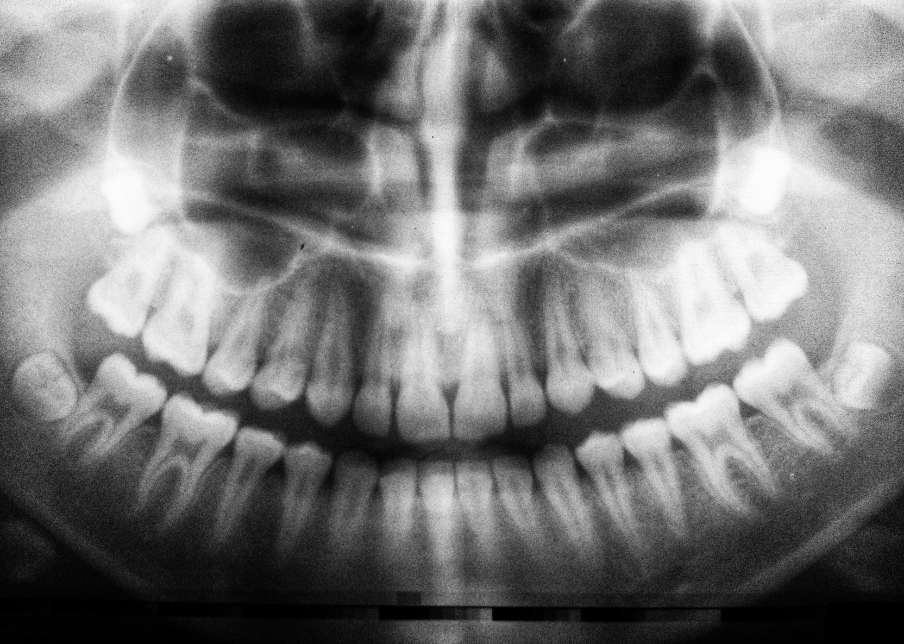

If your child is very young, we will first complete a visual examination and advise you if any decay is detected. This can be done since the primary teeth often do not touch, which means our dentist can see and feel the surfaces of your child’s tooth. If decay is visually detected we will then take digital X-Rays to determine the extent of the decay to prescribe the correct treatment plan for your child.